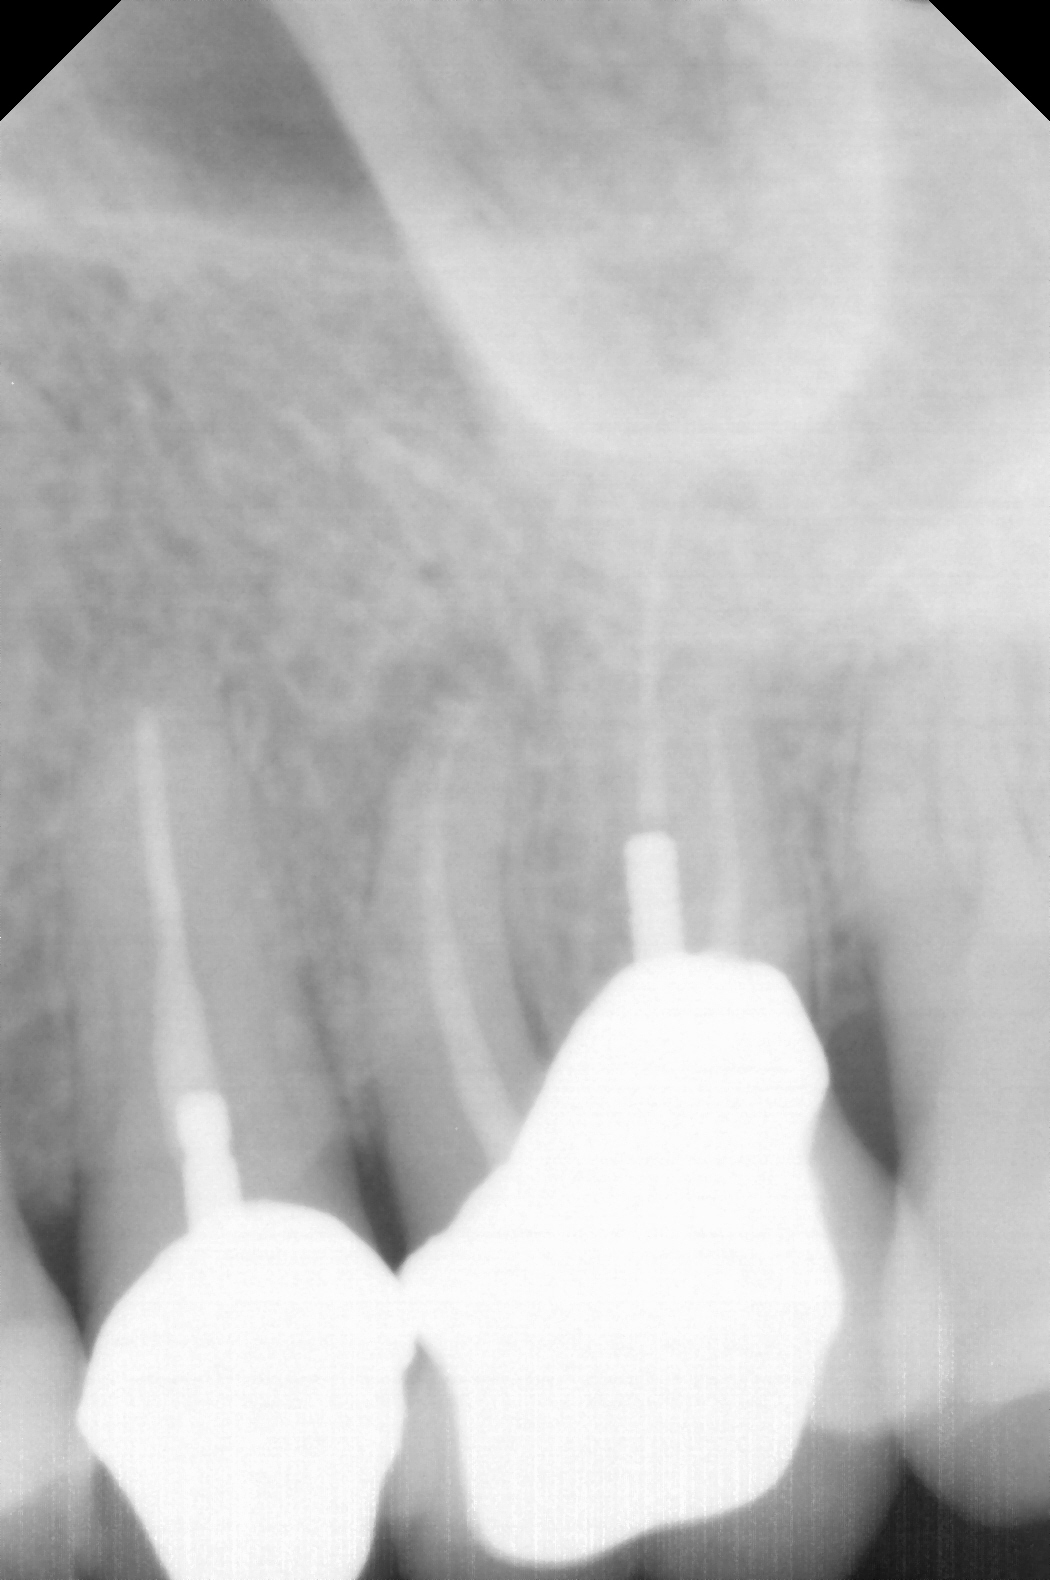

Fig 5. Working length confirmation.

Figure 5